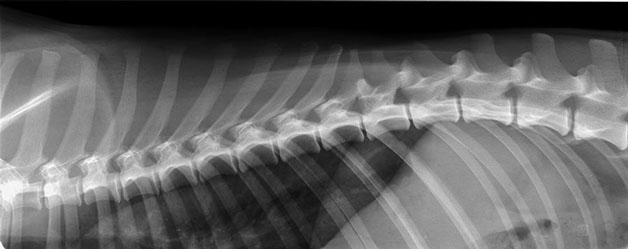

Radiographic Anatomy of the thoracic spine

(myelography right image)

latero-lateral projection

Click on the circles to see the answer

3rd rib (right)

Spinous process of T1

Articulation of the head of the rib 7 (left) with the body of T6 and T7